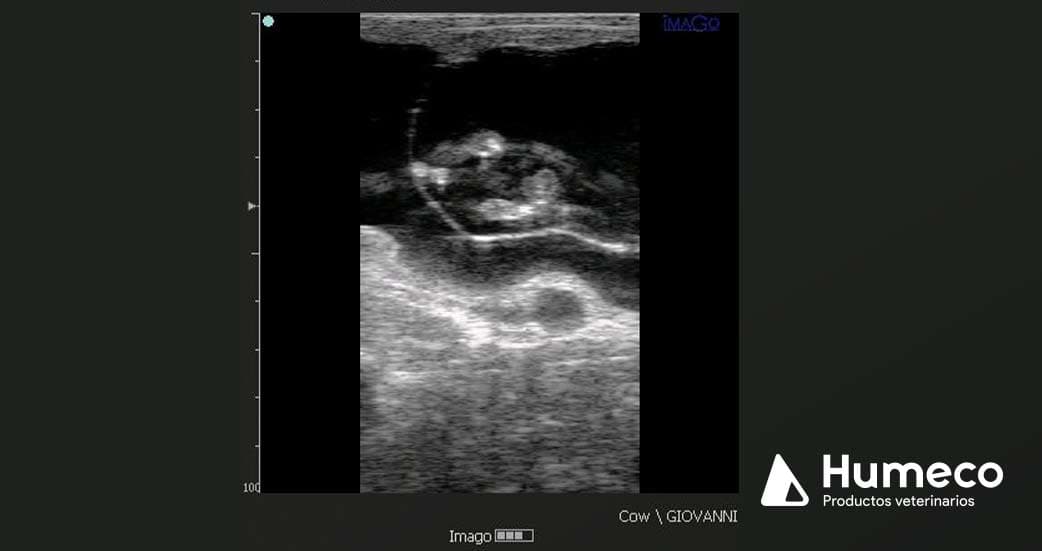

La prueba se llevó a cabo en vacas gestantes entre los días 55 y 110 de gestación, con un equipo de ultrasonido ultra portátil, IMAGO (ECM France), y con una sonda lineal de 5,0-7,5 MHz.

En cuanto a la determinación ecográfica del sexo fetal, se realiza de acuerdo con la posición del tubérculo genital, que comienza su migración desde la región inguinal, alrededor del día 45 de gestación, para localizarse en la hembra debajo de la cola entre los días 52 y 53 de gestación y,en el macho detrás del ombligo entre los días 54 y 56 de gestación.